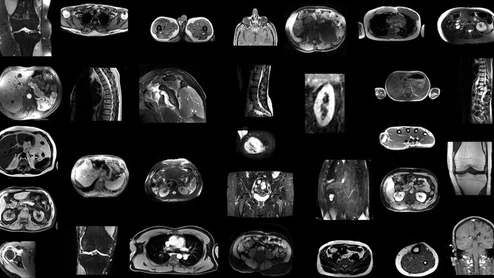

Hospital for Special Surgery pediatric MRI

The conclusions are based on an analysis of safety data from five leading pediatric hospitals, spanning 2017 to 2022, published in JACR